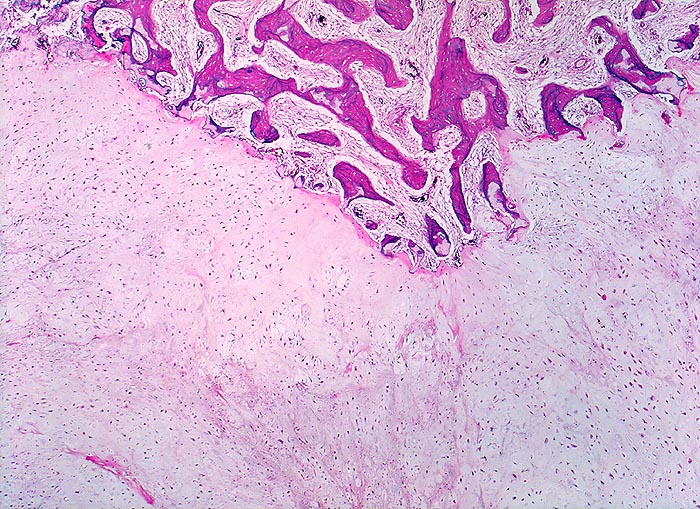

PathoPic – image database / PathoPic ID 4520 - hoch differenziertes Chondrosarkom

hoch differenziertes Chondrosarkom

Knochen, Rippe

Das Tumorgewebe (untere Bildhälfte) bildet reichlich helle chondroide Matrix. Die Zellularität im Tumor ist im Vergleich zu normalem Knorpel leicht erhöht und die Tumorzellen erscheinen etwas grösser als normale Chondrozyten. Das angrenzende Knochengewebe zeigt eine reaktive Markfibrose. An der Invasionsfront infiltriert und destruiert das Sarkom die Spongiosabälkchen.

Umschriebene Schmerzen im Bereich des Rippen-Thorax seit über einem Jahr.

Histologie

25

58

männlich